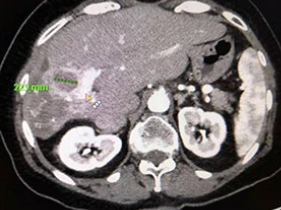

Surgnova tutkii ja kehittää aktiivisesti erilaisia tuumoriablaatioteknologioita. Surgnova on sitoutunut tarjoamaan maailman edistyneimmän ja täydellisimmän tuumoriablaatioalustan, jolla saavutetaan erinomainen ablaatiohoidon tarkkuus, monipuolisuus ja luotettavuus.

Patentoitu Dophi™ Anti-phase Technology mahdollistaa verrattoman ablaation ennustettavuuden, suuren tarkkuuden, toistettavuuden ja turvallisuuden eri kudostyypeissä.

- Suuri ja pallomainen ablaatioalue, patentoidun teknologian ansiosta